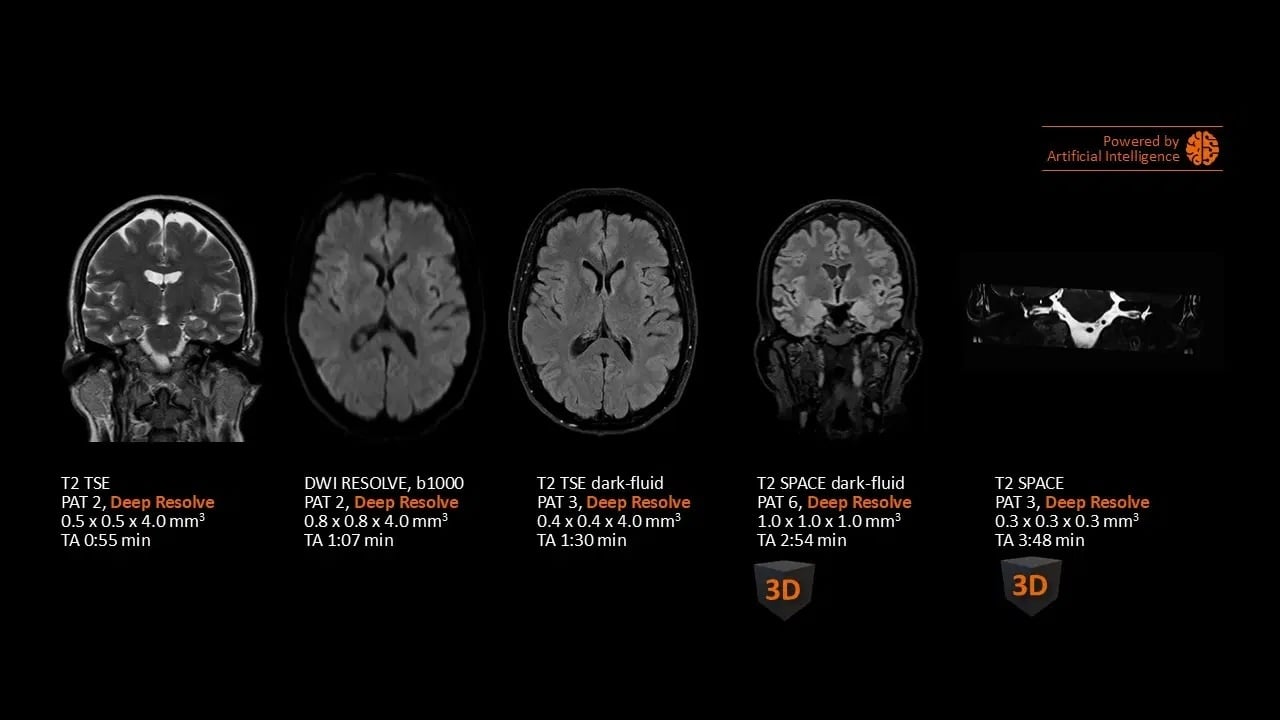

Head

Head exam with Deep Resolve 2D and 3D

Study-ID:1aaaa5199. Acquired on MAGNETOM Flow. Platform with 70cm.

Unrivaled speed with Deep Resolve

Deep Resolve, an AI powered tool used to boost signal and resolution, enables you to exploit advanced acceleration techniques while maintaining extraordinary clarity. Faster scans, faster results, better patient experience!